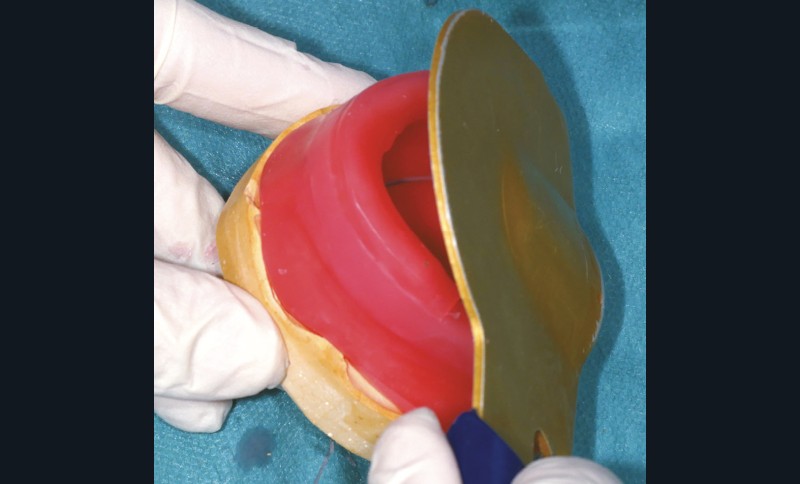

Le bourrelet doit être suffisamment rigide, tout en étant aisé à modifier. Il ne doit pas entraver le libre jeu de la musculature périphérique et les organes paraprothétiques (notamment la langue à la mandibule). On peut ainsi utiliser de la pâte de Kerr (marron ou blanche) ou d’un mélange de cire rose et d’une cire plus rigide (type Moyco). Certains auteurs proposent l’emploi d’un matériau thermoplastique type Stent’s afin de conserver une surface occlusale stable [11,17]. Les extrémités postérieures ne doivent recouvrir ni les tubercules rétro-molaires ni les tubérosités, et se terminer par des pans inclinés à 45° (fig. 4).

À la mandibule, le bourrelet suit la crête dans sa partie antérieure. Sa partie vestibulaire est concave et légèrement inclinée vers l’avant (sauf dans les cas de classe III où elle doit être dirigée vers l’arrière). La largeur du bourrelet est plus importante en postérieur (5 à 6 mm) qu’en antérieur (2 à 3 mm). La hauteur mesurée du bord incisif au fond de sillon est d’environ 18 mm. À l’arrière, le bourrelet doit s’arrêter aux deux-tiers du tubercule rétro-molaire (fig. 6).